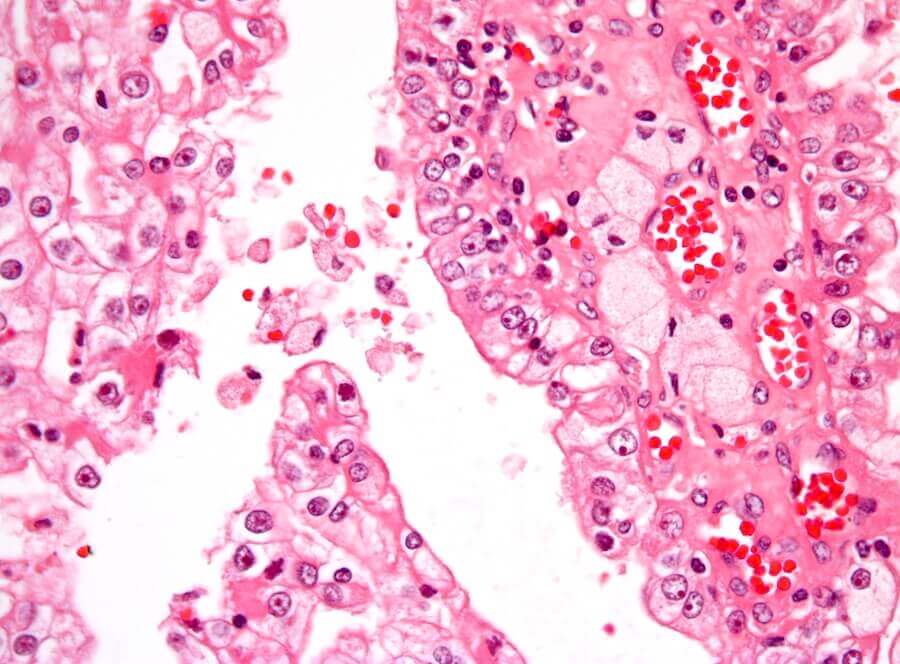

Cancer occurs when malignant cells multiply out of control in the body. The most common type of kidney cancer in childhood is called Wilms tumor or nephrolastoma. It’s solid and forms in the immature kidney tissue.